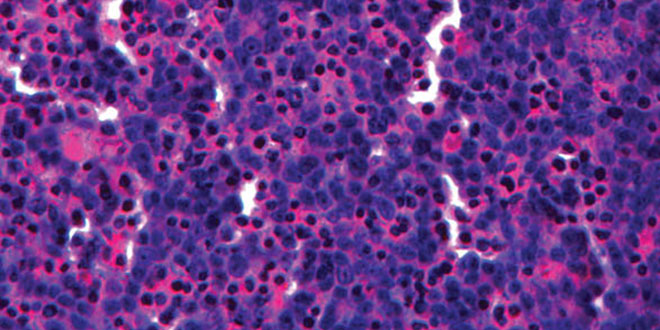

Cette collaboration aura pour but de mettre au point un premier rein imprimé en 3D et sera menée par le professeur Melissa Little de l’Institut de Bio-Science Moléculaire de l’Université du Queensland. Ces premiers reins pourraient notamment permettre de tester dans des conditions proches de la réalité la toxicité de certains traitements médicaux.

« Si nous pouvons tester la toxicité des médicaments sur les reins avant même de le tester sur l’homme, nous pourrions gagner beaucoup de temps, d’efforts et d’argent » explique Melissa Little avant d’indiquer que le but ultime serait bien évidemment de pouvoir imprimer des reins en vue d’être transplanté sur des humains, « il y a encore du travail pour y arriver mais une fois prêt cela pourrait sauver des vies et réduire largement le coût de certains traitements. »